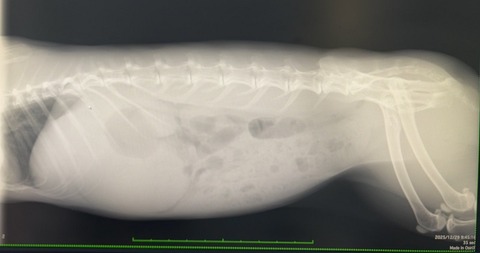

レントゲンと血液検査

胃拡張診断で点滴対応の日中入院となりました。